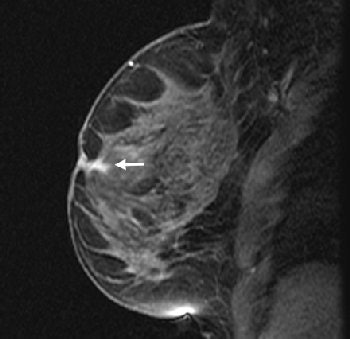

| Fifty-four-year-old woman with history of left breast cancer with normal mammogram and no palpable lumps, in whom MRI detected speculated right breast mass with no sonographic correlate. Sagittal fat-suppressed T1-weighted, contrast-enhanced scout image from MRI-guided biopsy shows 0.9 cm mass with speculated borders, irregular shape, and heterogeneous enhancement in right retroareolar region (arrow). |